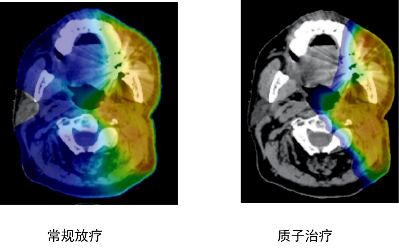

解析:这是头颈部肿瘤剂量分布图比较,我们明显能看到两者的差异,常规放疗蓝色区域很大,说明射线对病灶周边的正常组织有不可避免的损害,质子放疗可以减少咽喉和口腔部位的放疗损伤,降低发生口角炎、口腔炎、吞咽困难、口干的发生率。